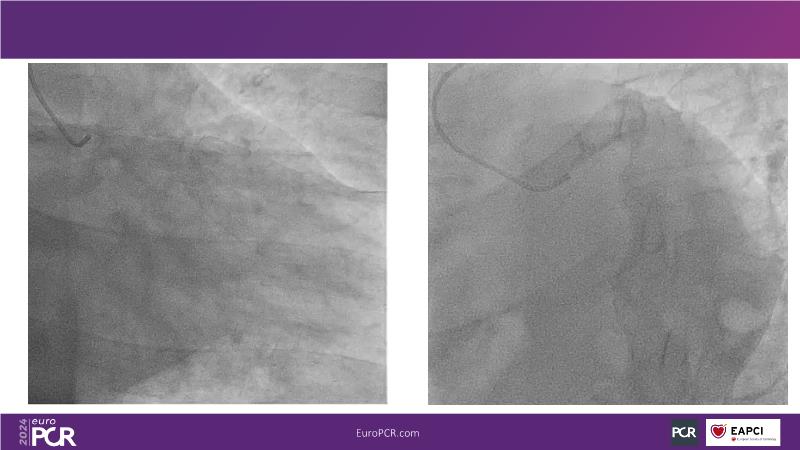

Tune in to this session to discover how reducing reliance on contrast opacification enhances procedural safety and enables more thorough revascularization in complex PCI scenarios. Learn that ultra-low contrast (ULC) PCI encompasses various interventional skills and specialized tools, many already familiar to interventional cardiologists. Embrace a mindset shift, starting with applying ULC PCI principles in simple cases and progressing to complex interventions.

- To share the principles of PCI through recorded cases to better understand how they work in practice